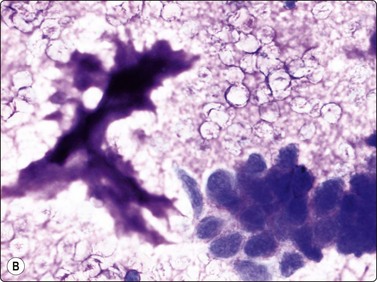

image image

Fig. 16.10 Langerhans cell histiocytosis (eosinophilic granuloma)

(A) Lytic bone lesion, many histiocytes with irregular reniform pale nuclei, some eosinophils (H&E, IP); (B) Coffee-bean nuclei have been reported to be typical of this lesion (H&E, HP, Oil)

The Langerhans cell histiocytes express S-100 protein and CD1-antigen (Fig. 16.11). According to the Histiocyte Society the definitive diagnosis of Langerhans cell histiocytosis is based on the demonstration of Birbeck granules by electron microscopy or positivity for CD1 antigen.15 The examination of conventionally stained material gives a presumptive diagnosis. The cytological features of Langerhans cell histiocytosis has been recorded in several series.16-18

Fig. 16.11 Langerhans cell histiocytosis (eosinophilic granuloma)

The Langerhans cell histiocytes express (A) S-100 protein and (B) CD1-antigen (Cell block, immunoperoxidase).